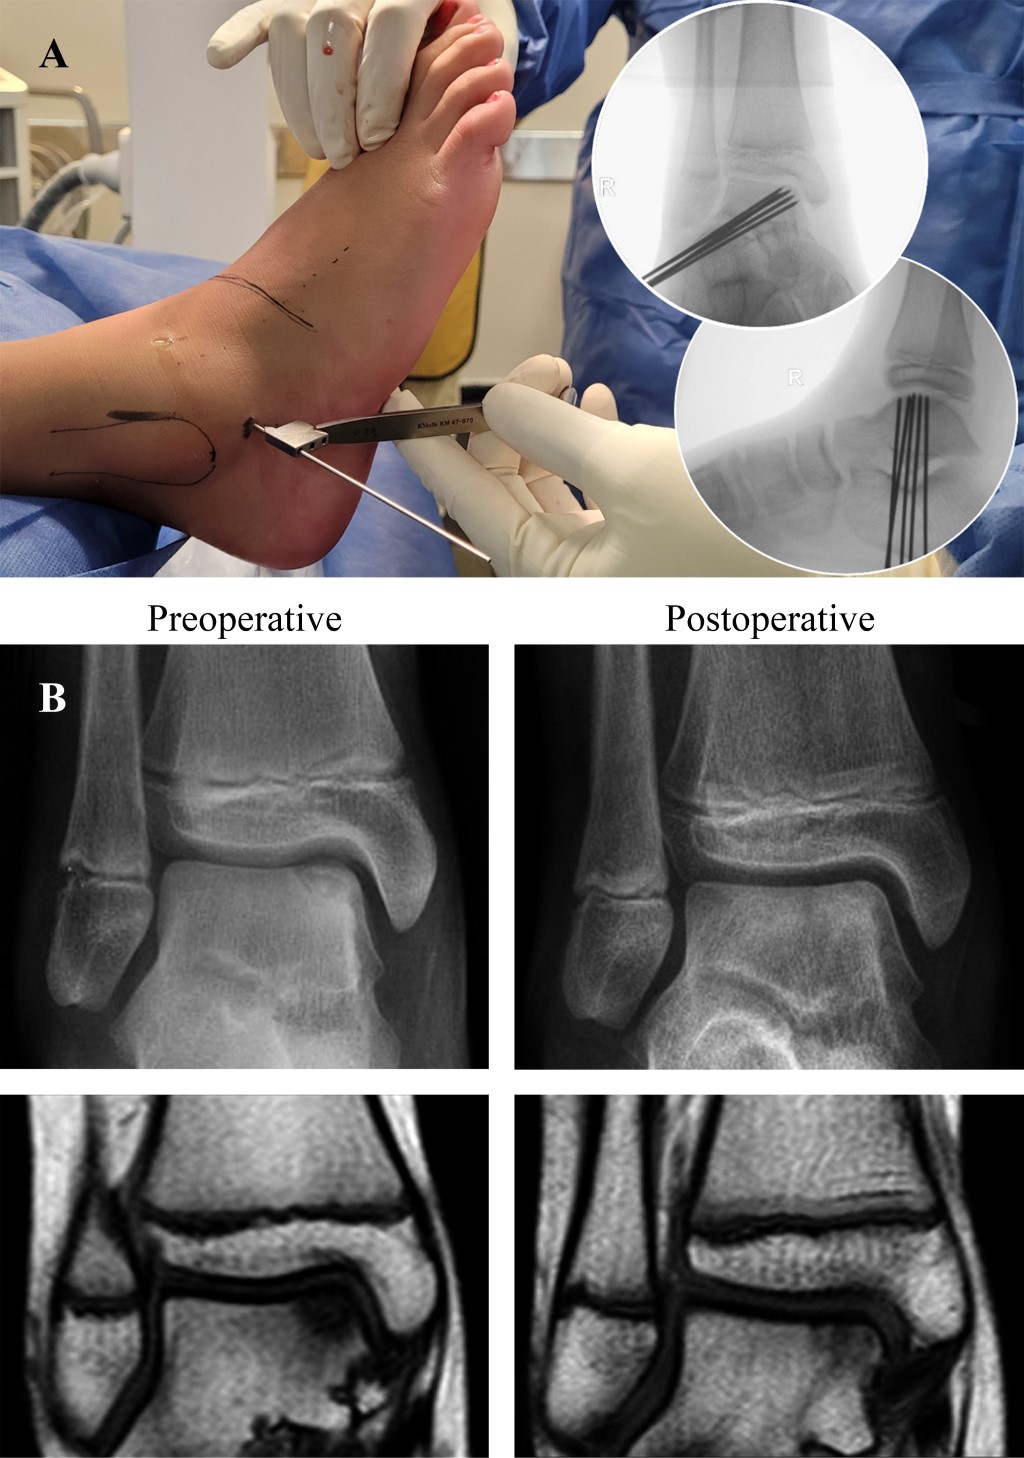

Figura 2